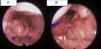

Tras 2 meses de buen cumplimiento terapéutico, persiste disfonía con ronquido nocturno, realizándose una fibrolaringoscopia que mostró imágenes compatibles con tuberculosis laríngea (fig. 1). Control de cultivos de esputo inducido negativos, mejoría radiografía de tórax y PCR normal. Ante esta reacción paradójica postratamiento correcto, se asoció prednisona 4 semanas a dosis de 1mg/kg/día, con pauta descendente posterior, observándose rápida mejoría (fig. 2).

Aspecto de la laringe después del tratamiento con corticoides. A) Se aprecia una reducción significativa de la inflamación de la epiglotis (punta de flecha), mejorando de forma apreciable la luz a nivel del vestíbulo laríngeo (asterisco). B) Recuperación del aspecto normal de la cuerda vocal derecha (punta de flecha).

Aunque la respuesta al tratamiento antituberculoso suele ser suficiente, algunos casos descritos precisaron microcirugía laríngea para corregir la disfonía2,3. En nuestra paciente, asociar corticoides ayudó a mejorar esta complicación local.